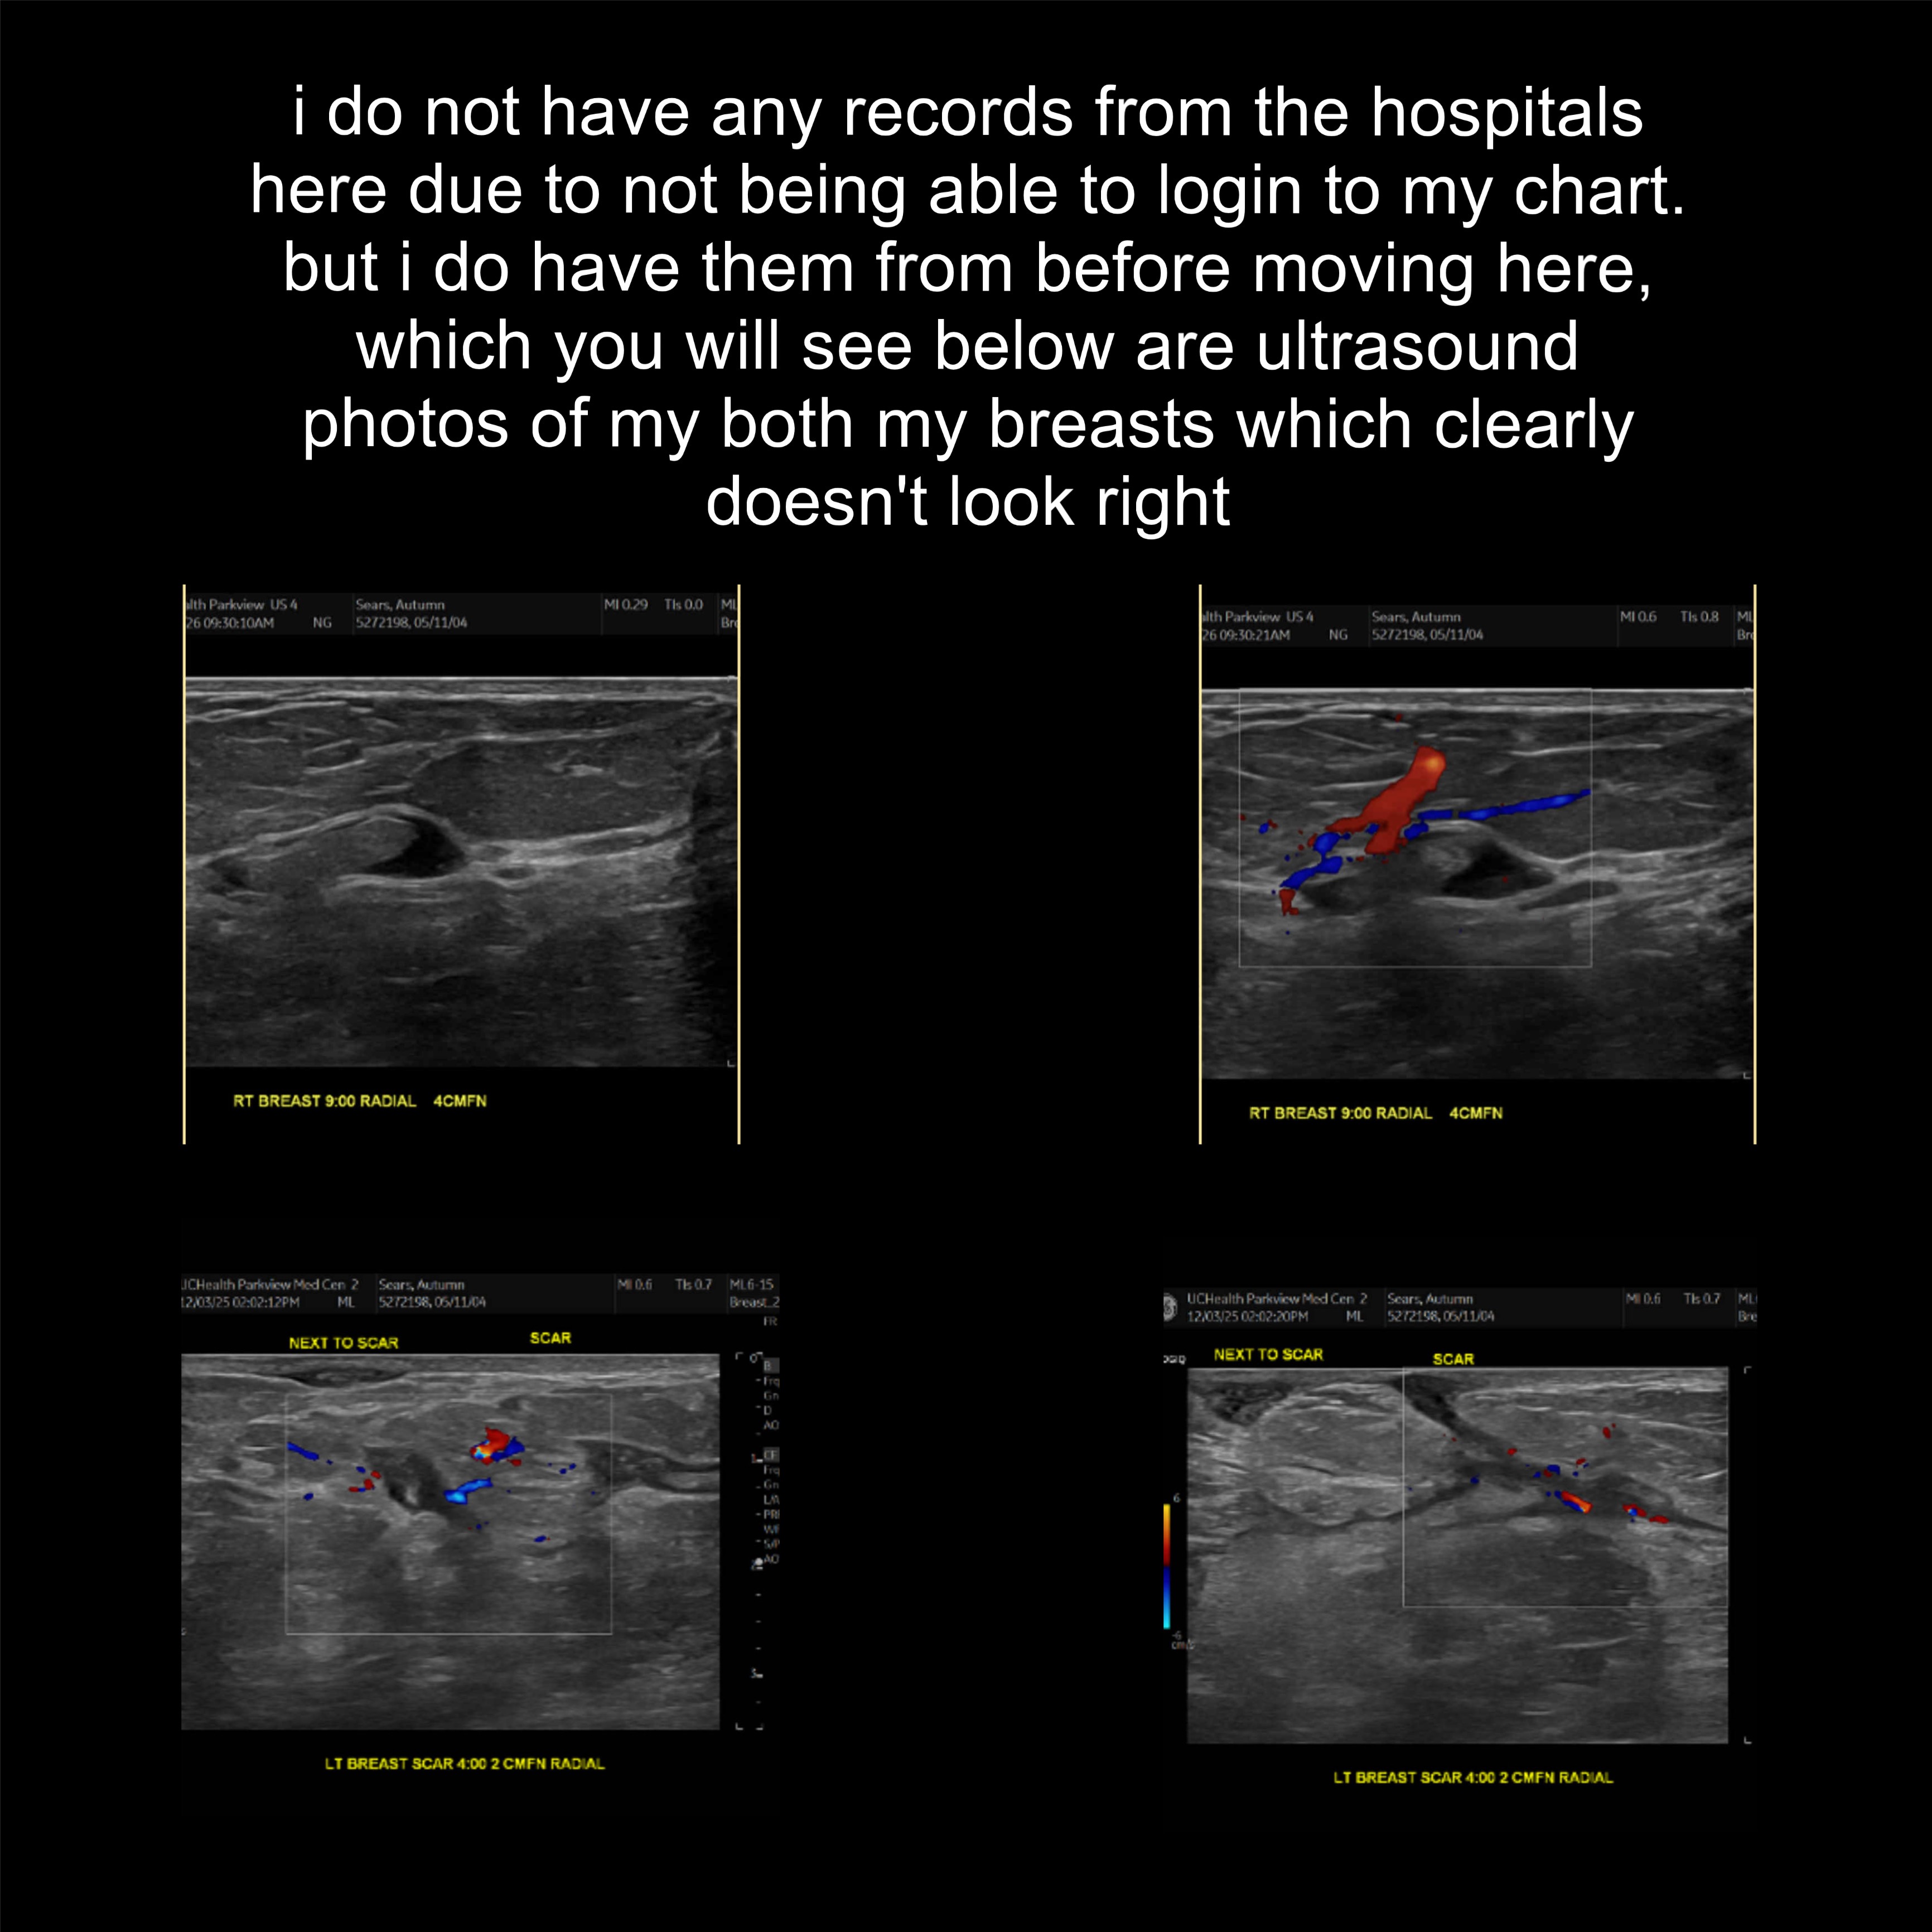

hello my name is autumn, i go by aki online, ive been dealing with possible breast cancer since mid august, ive had two surgeries two weeks apart in september and october to attempt to remove whatever im dealing with in my left breast. after that the hospitals where i was at didn't seem to do anything else to help and marked me as a druggie when i was sobbing in pain asking for better pain meds.